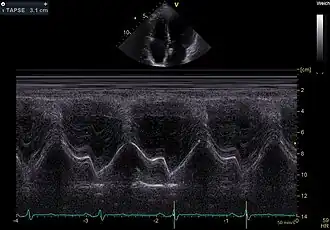

TAPSE

TAPSE ist eine Akronym für tricuspid annular plane systolic excursion, einen Messwert in der Echokardiografie mit dem die Kontraktionsfähigkeit (systolische Funktion) der rechten Herzkammer beschrieben werden kann. Hierbei wird im apikalen 4-Kammer-Blick mit dem M-Mode die Bewegung des lateralen / anterioren Trikuspidalklappenanulus gemessen als Maß für die Verkürzung des rechtsventrikulären Myokards bei der Kontraktion.

Als normal werden Werte über 1,7 cm angenommen.[1]